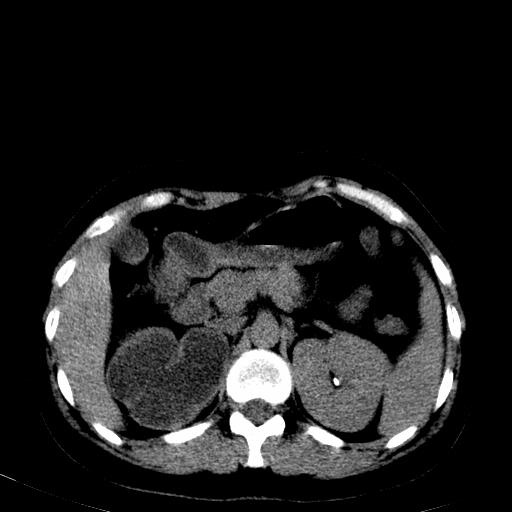

右肾重度积水,以肾盏积水明显,有分隔,上段输尿管轻度扩张,管壁增厚,考虑肾结核可能,请结合尿检查,胸部拍片排除肺结核。

右肾重度积水,建议ct向下扫描或逆行造影,左肾及左输尿管结石 .

1)不排除右肾结核可能。2)左肾及左输尿管上段结石?

结合强化图片看ivp意义不大,建议作逆行造影看一下;

左肾不是结石,是造影后改变.右肾积水,功能仅存.